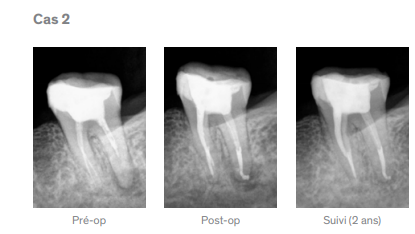

Contrairement aux ciments d’obturation conventionnels, la réaction de prise du TotalFill BC Sealer est déclenchée par l’humidité présente dans les tubulis dentinaires. En utilisant cette humidité, le TotalFill BC Sealer permet la formation d’hydroxyapatite assurant une adhérence chimique optimale entre la dentine et le ciment.

– Liaison entre le ciment et la dentine

– Liaison entre le ciment et les TotalFill BC Points